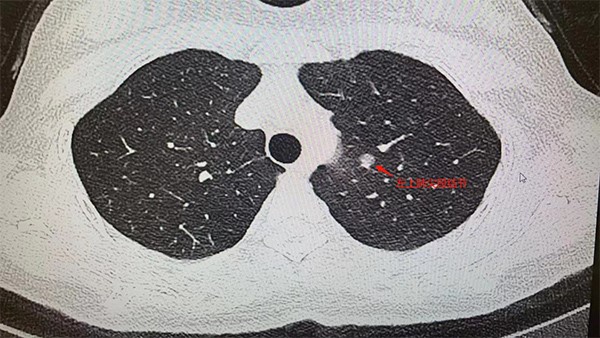

據了解,王女士今年5月在重慶市某三甲醫院做例行體檢時,低劑量胸部CT顯示:左肺上葉尖后段有7mm*6mm的磨玻璃結節,性質待定。醫生表示有肺癌可能性,建議進一步診治。肺結節這么小,到底切不切?10月24日,王女士來到重慶西區醫院胸外科主任姚珂門診隨訪。

患者胸部CT檢查圖片。重慶西區醫院供圖

姚珂介紹,結合影像學特征,王女士的肺小結節,惡性征象明顯。制定手術方案時,姚珂考慮到該患者病灶靠近主支氣管,位置較深,需要游離的血管較多,為保證精準切除病灶且最大程度保護患者肺功能,通過穿刺定位+CT三維重建引導,行單孔胸腔鏡下肺聯合亞段切術,最為合適。目前,手術取得成功。